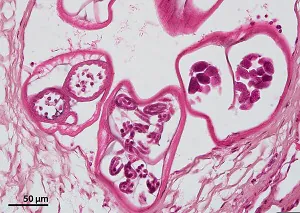

Brugia spp. have typical features of filarial nematodes in cross-section. Females reach a maximum diameter of 180 µm; males are smaller (up to 90 µm). The intestine is small and females have two uterine tubes containing developing microfilariae. The musculature is comprised of few coelomyarian cells per quadrant and the cuticle is smooth.